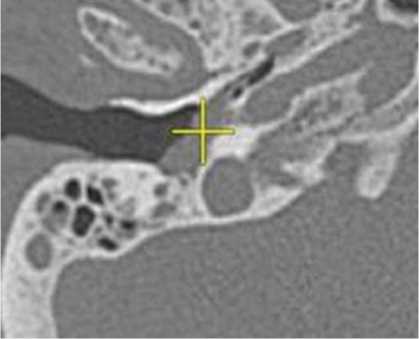

Пациенты третьей группы с диагностированной распространенной параганглиомой предъявляли жалобы на отсутствие слуха с пораженной стороны, периодическое онемение лица, периодические эпизоды кровотечения из слухового прохода. У 6 пациентов, которые до поступления в нашу клинику неоднократно подвергались хирургическим вмешательствам, отмечался парез лицевого нерва со стороны поражения, который соответствовал 5–6 степени по шкале House – Brackmann. При отоскопии у пациентов определялось выпирающее в просвет наружного слухового прохода красно-бордовое пульсирующее объемное образование. По данным лучевых исследований, на КТ височных костей у пациентов определялся мягкотканный субстрат, заполняющий барабанную полость. Крыша барабанной полости была истончена, местами не определялась (1). Костная стенка канала внутренней сонной артерии не прослеживалась. На уровне луковицы яремной вены определялось мягкотканное образование, которое разрушало костные стенки гипотимпанума (2) (рисунок 5).

Рисунок 5. КТ правой височной кости, аксиальная проекция. Параганглиома, тип С: задняя стенка нижнечелюстной ямки местами не определяется (1). На уровне яремной ямки определяется мягкотканное содержимое, которое разрушает костные стенки гипотимпанума (2).